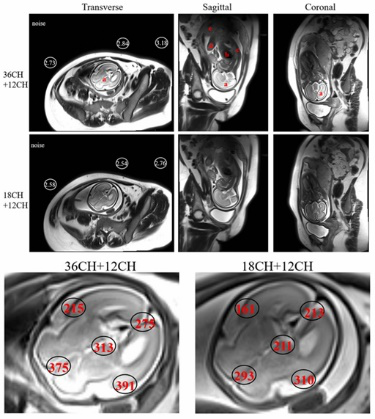

磁共振胎儿成像可发现复杂先天性疾病,尤其对神经发育异常和心血管疾病诊断有不可替代的价值。现有磁共振技术在成像速度和图像信噪比方面对于胎儿成像有较大的局限性。团队基于高灵敏电子设计了大范围、高密度多通道新型表面柔性线圈,与商用的线圈对比,设计的线圈的图像信噪比提高可达40%左右,更多的线圈单元可以显著提高成像速度,成功实现了清晰的胎儿大脑(2倍加速)和心脏电影(4倍加速)成像。相关成果发表在IEEE Transactions on Medical Imaging,第一作者为陈巧燕,通讯作者为郑海荣、李烨。

图2 设计的36通道线圈(结合12通道脊椎线圈)与商用的18通道线圈(结合12通道脊椎线圈)的胎儿大脑(2倍加速)成像结果对比,36通道线圈可以明显提高图像信噪比,高达40%左右。

图3 设计的36通道线圈(结合12通道脊椎线圈)采集的胎儿心脏成像(4倍加速)结果。